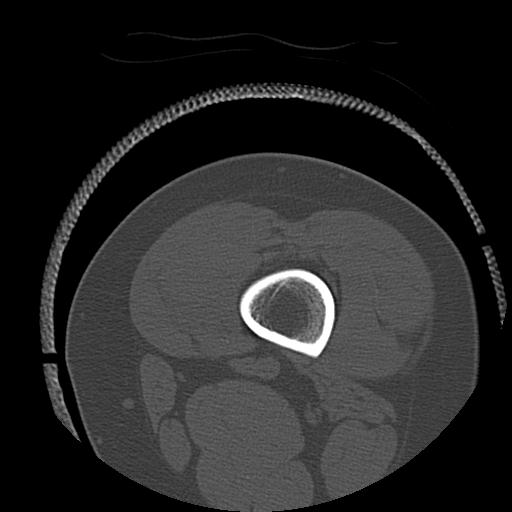

56476 8/28 4R 1/21 2R 左足関節 デジカメ写真 72歳女性 右足関節AS